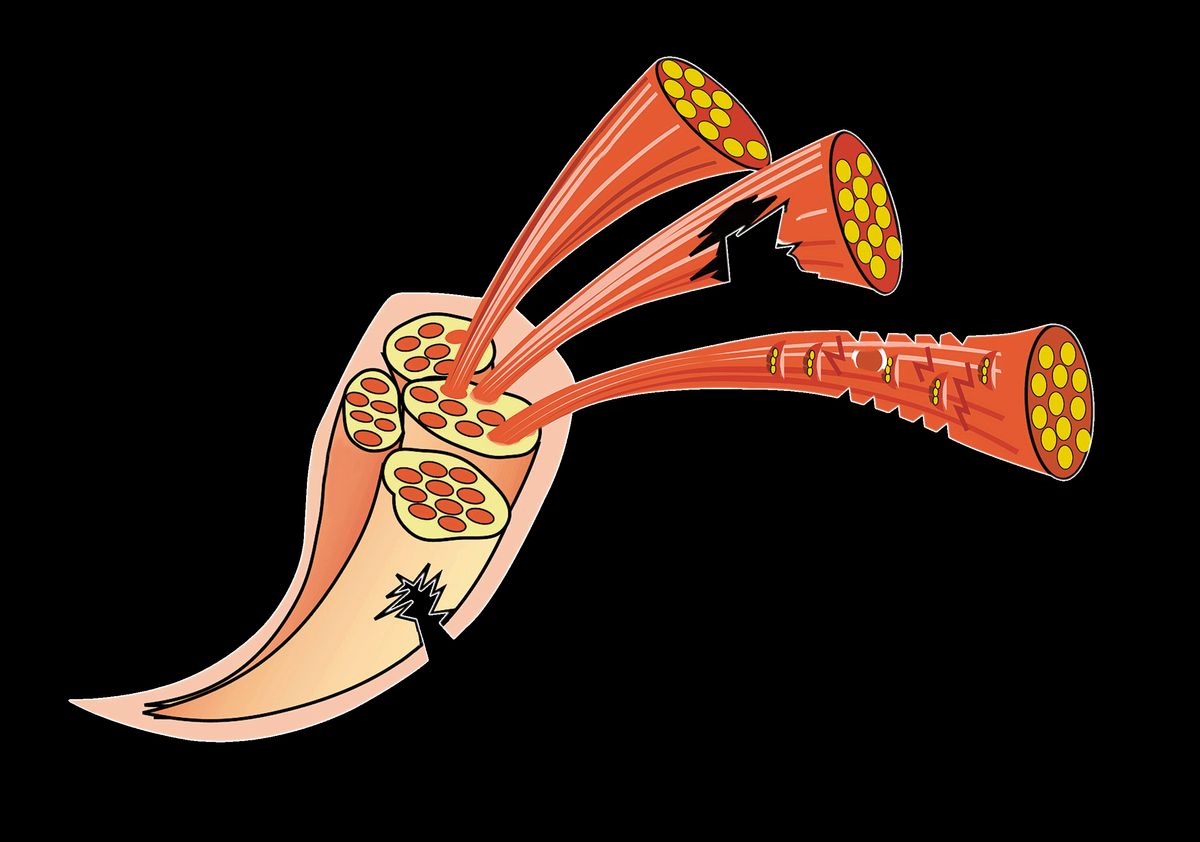

„Eine ausreichende Zeit des Auskurierens ist extrem wichtig bei Muskelverletzungen“, stellt Dr. Thorsten Rarreck, Mannschaftsarzt des FC Schalke 04, klar. Muskel stark überdehnt: Zunächst mal ist aber die Diagnose entscheidend, denn grundsätzlich liegt allen Muskelverletzungen dieselbe Ursache zugrunde: eine Dehnung des Muskels, die über das „normal verträgliche“ Maß hinausgeht. Doch was genau unterscheidet einen Bündelriss von Zerrung oder Faserriss? Was genau passiert dabei in der Muskulatur? Und was sind die möglichen Folgen? Hier gibts die Antworten!!!

"Die Art des Schmerzes hängt zunächst mal vom Patienten ab. Allerdings gibt es je nach Schwere der Muskelverletzung typische Muster", erklärt Dr. Thorsten Rarreck, der Teamarzt von Schalke 04. Während sich etwa bei einer Zerrung der Muskel kurz krampfartig zusammenzieht (ohne starken Schmerz), fühlt man beim Muskelfaser- oder Muskelbündelriss auf Anhieb einen deutlichen, schmerzhaften Stich, der die Zerstöung im Muskel erahnen lässt.